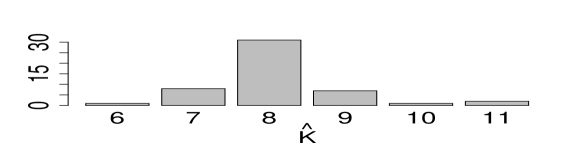

Inference summaries are reported in Figure 5. Figure 5(a) shows the posterior distribution of the number of latent diseases. The posterior mode occurs at the true value . Conditional on , the posterior point estimate is displayed in Figure 5(e) with mis-allocation rate 111The percentage is computed based on free parameters in only.. Conditional on , the point estimates and are provided in Figures 5(f) and 5(g). The similarity between the heatmaps of the simulation truth and estimates indicates an overall good recovery of the signal. The error rates in estimating and are 0% and 2%, respectively. We repeat this simulation 50 times. In 96% of the repeat simulations, we correctly identify the number of latent diseases; in the remaining 4%, it is overestimated by 1. When is correctly estimated, the average mis-allocation rate, error rates for and are 3%, 1% and 1% with standard deviation 0.5%, 1% and 1%, respectively. We provide addtional simulation studies in Supplementary Material A to investigate the performance of DFA with different hyperparameters and with the alternative prior that was introduced in (3).

We ran the MCMC algorithm described in Section 4 for 50,000 iterations. The first half of the iterations are discarded as burn-in and posterior samples are retained at every 5th iteration thereafter. Goodness-of-fit and MCMC convergence diagnostics show adequate fit and no evidence for lack of convergence (Supplementary Material B). Posterior probabilities for the number of latent diseases are and , respectively, i.e., the maximum a posteriori (MAP) estimate is . This includes the 4 a priori known diseases as well as 10 newly discovered latent diseases.